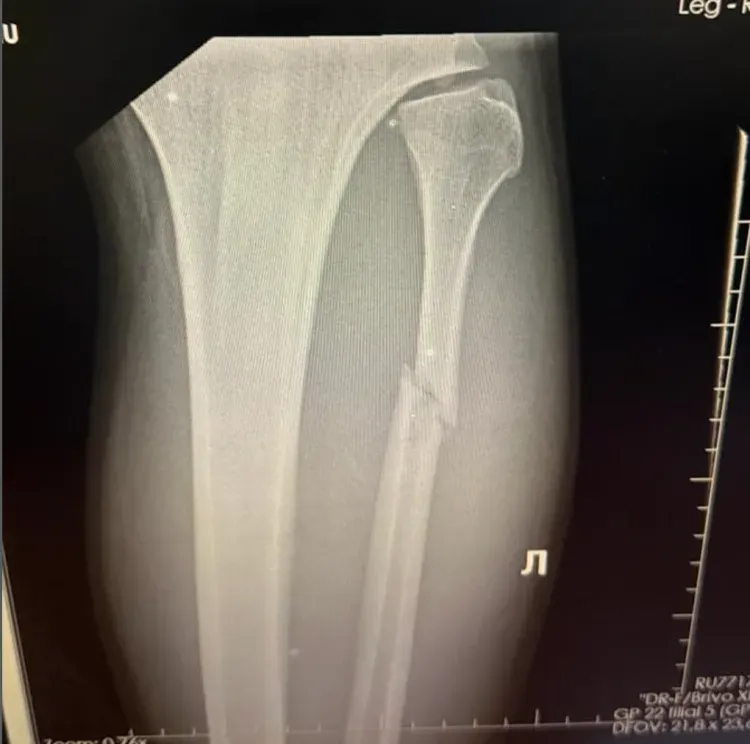

Ce n'est qu'après une visite chez le médecin et une radiographie que la vérité a éclaté, choquant Walker lui-même. « Quand le médecin m'a montré l'image, je n'y croyais pas. Je me suis dit : "Quoi ? Ma jambe est cassée ?" »

Valter Walker évite l'opération, expliquant que l'os n'est heureusement « pas complètement brisé en deux ». Un plâtre et cinq à six semaines de repos sans appui suffiront, mais s'il force, l'os pourrait bouger et la chirurgie deviendrait nécessaire.

Heureusement, la fracture ne nécessite pas d'opération, mais un plâtre et cinq à six semaines de repos sans appui sur la jambe. Ce repos forcé est un défi mental pour le combattant, qui admet n'avoir jamais pris plus de trois jours sans entraînement en six ans de carrière. « Je veux aller à la salle », a-t-il admis, mais son équipe le contraint à une semaine de repos complet. Il espère désormais un retour dans l'octogone en février ou mars 2026.